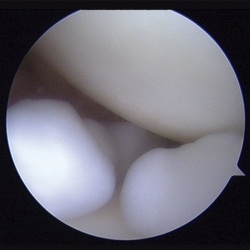

Se realizaron radiografías anteroposterior y axial de hombro, objetivándose calcificaciones intraarticulares, redondeadas, bien delimitadas. Ante dichos hallazgos, se procedió a la realización de una resonancia magnética (RM). En dicha prueba se objetivaron lesiones quísticas múltiples, bien delimitadas, algunas de ellas isointensas en T1, junto a otras lesiones hipointensas en T1 y T2 en la articulación glenohumeral compatibles con el diagnóstico de condromatosis sinovial (Figuras 1 y 2).

Con el diagnóstico de condromatosis sinovial de hombro derecho se procedió a la realización de una artroscopia, viendo múltiples cuerpos libres intraarticulares, la mayoría de ellos de consistencia cartilaginosa (Figuras 3 y 4) y se procedió a su extracción por vía artroscópica (Figura 5). Tras la cirugía, se remitió a la paciente a recuperación funcional, presentando una buena evolución clínica. La paciente se encuentra asintomática en el momento actual, presentando un balance articular completo.

Figura 3. Imagen artroscópica: cuerpos libres en condromatosis sinovial.

Figura 4. Imagen artroscópica: cuerpos libres en condromatosis sinovial.